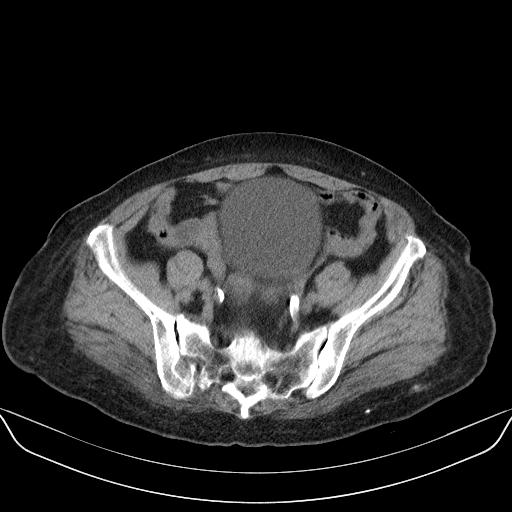

以下是引用yuhongjun在2010-3-12 6:32:00的发言:[br]回肠末端间质瘤,不除外阑尾粘液囊腺瘤,臀部注射性肉芽肿钙化. [br] [br]